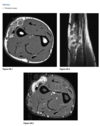

Radiographs of the right tibia and fib-

ula (Figs. 2.21.1 and 2.21.2) show a vague, irregu-

lar linear radiolucency within an area of sclerosis

in the distal third of the tibia (arrowheads). Coronal

T1-weighted MRI of the tibia reveals a serpiginous

region of decreased marrow signal extending over

several centimeters (Fig. 2.21.3, arrows) and a de-

fect in the lateral tibial cortex (curved arrow). Axial

T2-weighted MRI through the same region demon-

strates a bony sequestrum (Fig. 2.21.4, arrowhead)

and increased signal intensity (i.e., marrow edema)

within the tibia. A sinus tract extends through the

lateral aspect of the posterior tibia (white arrow) to

the skin surface anteriorly (black arrow), with edem-

atous changes in the subcutaneous tissues.

Chronic osteomyelitis with a draining

sinus tract

In acute

osteomyelitis, the earliest radiographic sign is ob-

scuration of the normal fat planes as a result of soft-

tissue swelling. Bony changes usually do not appear

until 1 to 2 weeks after the onset of the infection.

Osteomyelitis typically affects the epiphysis in in-

fants and adults and the metaphysis in children and

is multifocal in neonates. The MRI features of acute

osteomyelitis include areas of diminished signal in-

tensity on short TE images within the normally high.

signal intensity of the fatty bone marrow. Long TE

images with fat-suppression or inversion-recovery

images usually show areas of increased signal inten-

sity in muscle, cortical bone, and periosteum that

are not well demonstrated on short TE sequences.

T1-weighted fat-suppressed, gadolinium-enhanced

images increase sensitivity and specificity in the di-

agnosis of infection.

The radio-

graphic findings of chronic osteomyelitis include

prominent cortical thickening and a mixed pattern

of osteosclerosis and osteolysis. Signs suggesting re-

activation of infection include the development of

new, ill-defined areas of osteolysis; thin, linear peri-

ostitis; or the presence of a sequestrum and draining

sinus tract.

An unusual complication of a long-standing

draining sinus tract in chronic osteomyelitis is squa-

mous cell carcinoma.